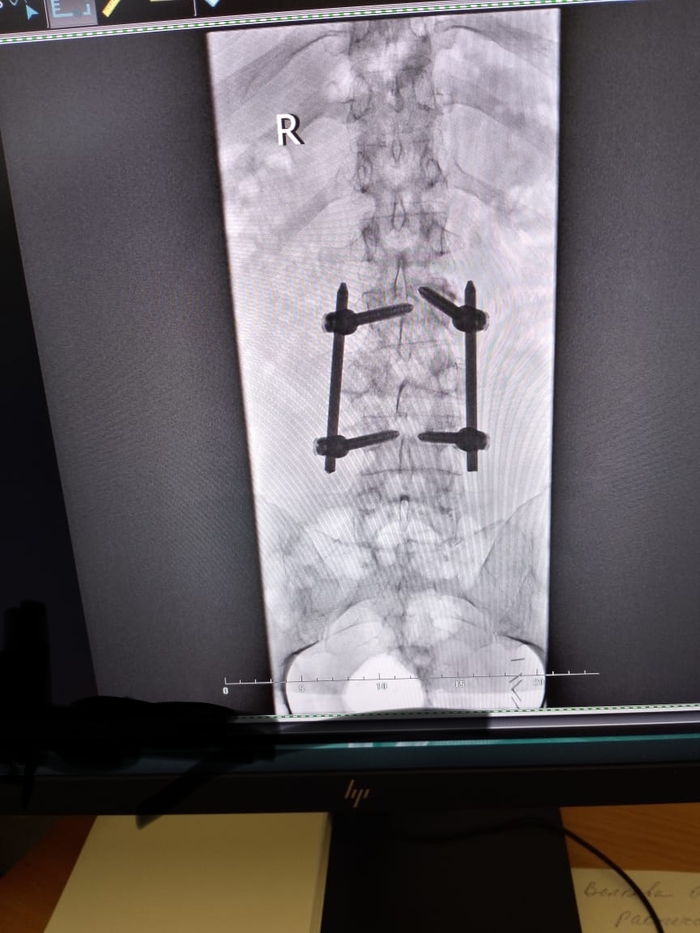

В течении года продолжалось восстановление- таблеточки, витаминчики. Из улучшений- меньше стала болеть нога, отросли волосы, прошли побочки химии. Со спиной все по разному, боли то есть то нет и появилась грыжа Шморля- как сказал ортопед , она появилась из за того что конструкция ослабла и болт один просел и царапает позвонок и из за этого боли и грыжа ( но болт поцарапает до определённого момента и перестанет , и боли пройдут). Еще сказал что можно или удалить всю эту конструкцию или распространить на позвоночник дальше, но это по рекомендации онкологов- нужно ехать в Москву и там консультироваться с онко и ортопедами( а это лишние деньги, возможно после нового года поеду). В конце ноября был куплен велотренажёр, и спустя пару недель занятий больная нога стала работать лучше, смог отталкиваться - очень большой плюс. Из минусов ещё появились проблемы со зрением, выявили астигматизм и прописали очки но носить не могу так как начинает тошнить..

В понедельник был на кт, изменений никаких нет по онкологии - все так же стабилизация, только нашли грыжу Шморля.